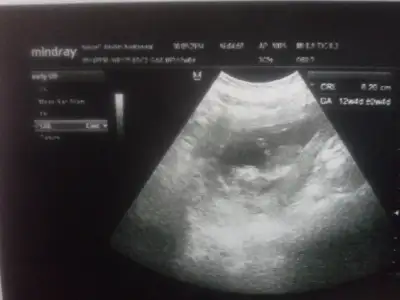

% 90 erkekArkadaşlar cinsiyet yorumu yapabilecek var mı? Lütfen yardım !!

Canım benim bebişinde cinsiyetini tahmin edebişirmisin% 90 erkek![]()

Banada bi bakarmisin canim.cok merak ediyorum% 90 erkek![]()